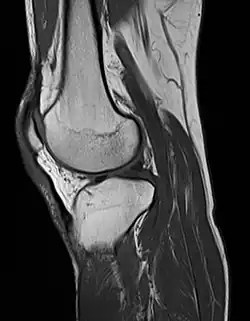

MRI uses strong magnetic fields to align atomic nuclei (usually hydrogen protons) within body tissues, then uses a radio signal to disturb the axis of rotation of these nuclei and observes the radio frequency signal generated as the nuclei return to their baseline states.[15] The radio signals are collected by small antennae, called coils, placed near the area of interest. An advantage of MRI is its ability to produce images in axial, coronal, sagittal and multiple oblique planes with equal ease. MRI scans give the best soft tissue contrast of all the imaging modalities. With advances in scanning speed and spatial resolution, and improvements in computer 3D algorithms and hardware, MRI has become an important tool in musculoskeletal radiology and neuroradiology.

One disadvantage is the patient has to hold still for long periods of time in a noisy, cramped space while the imaging is performed. Claustrophobia (fear of closed spaces) severe enough to terminate the MRI exam is reported in up to 5% of patients. Recent improvements in magnet design including stronger magnetic fields (3 teslas), shortening exam times, wider, shorter magnet bores and more open magnet designs, have brought some relief for claustrophobic patients. However, for magnets with equivalent field strengths, there is often a trade-off between image quality and open design. MRI has great benefit in imaging the brain, spine, and musculoskeletal system. The use of MRI is currently contraindicated for patients with pacemakers, cochlear implants, some indwelling medication pumps, certain types of cerebral aneurysm clips, metal fragments in the eyes, some metallic hardware due to the powerful magnetic fields, and strong fluctuating radio signals to which the body is exposed. Areas of potential advancement include functional imaging, cardiovascular MRI, and MRI-guided therapy.